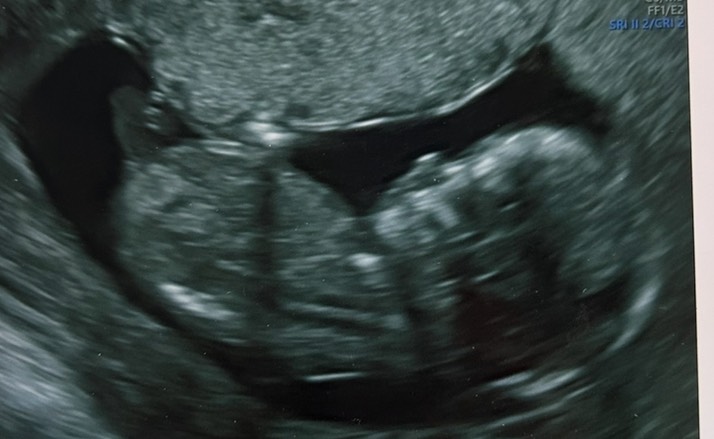

Сходила на первый скрининг

По узи все хорошо, очень этому рада

Сказали, что у нас девочка будет))) не знаю, верить или нет, вдруг ошиблись. У кого совпал пол с 1 скринингом ?